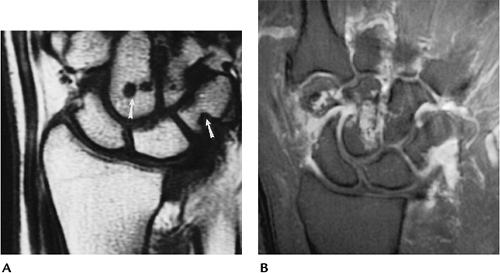

FIGURE 9-45 Rheumatoid arthritis. (A) Early changes in the wrist with soft tissue swelling and erosions (arrowheads). (B) Advanced rheumatoid arthritis with carpal collapse and erosion of the distal radius and ulna.

FIGURE 9-46 Rheumatoid arthritis. (A) Coronal T1-weighted image demonstrating erosions (arrows) not apparent on radiographs. (B) Contrast-enhanced image shows enhancing synovium and carpal erosions in the capitate and trapezium.